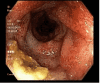

Figure 3

Figure 3. Descending colon: erythematous, edematous and friable mucosa with loss of vascularity, and superficial ulcerations with exudate, as well as multiple small-mouthed diverticula